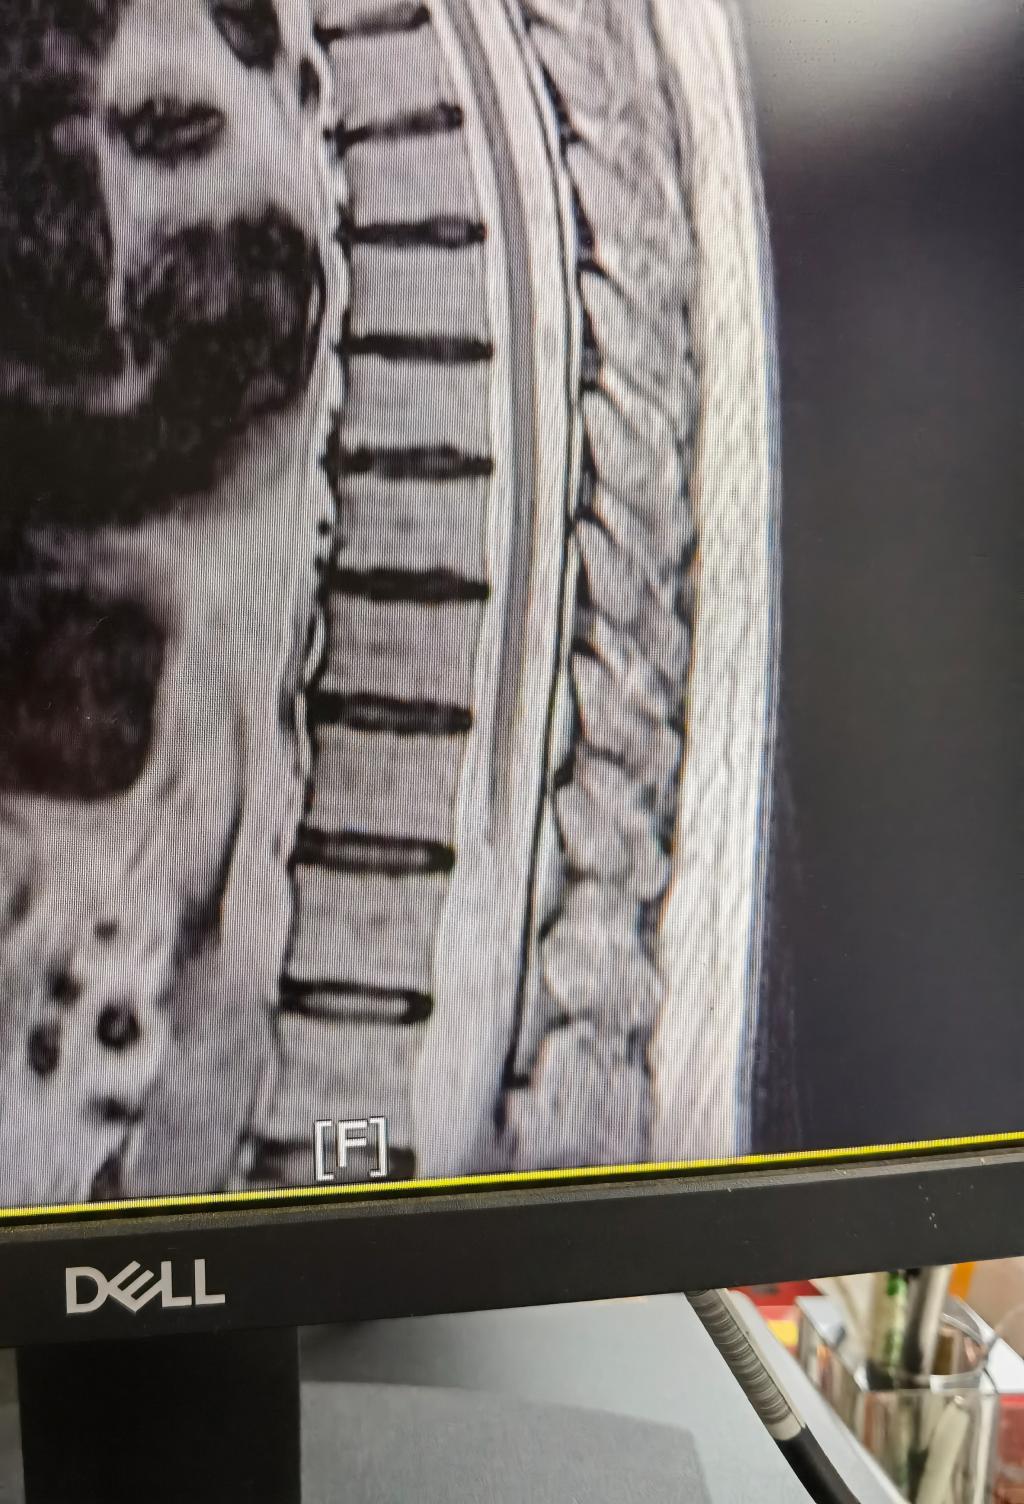

一周前,区医院神经内科收治了一名59岁的男性患者,4年前开始出现双下肢麻木等不适,该患者分别前往新疆各大医院进行诊治,经多种治疗后,症状一直未见缓解且进行性加重。患者家属听说区医院有西安交通大学的专家后,患者抱着试一试的态度前来自治区医院就诊,因为病史较长且疗效不佳,神经内科遂请脊柱一科联合会诊,我院驻疆专家杨宝辉副主任医师同全科医生仔细查看患者影像资料等后,高度怀疑患者系硬脊膜动静脉瘘,并建议行脊髓血管造影进一步确诊。后经DSA检查结果支持我院驻疆专家的会诊意见,该患者确诊为胸12部位硬脊膜动静脉瘘,为下一步该患者的治疗提供了宝贵的科学依据,起到事半功倍的效果。

硬脊膜动静脉瘘是近 20 年来才逐渐被业内认识的一种椎管内血管畸形,是指供应神经根或硬脊膜的动脉在椎间孔处穿过硬膜时与脊髓引流静脉形成交通 。由于SDAVF 发病率极低,文献报道年发病率 5~10人 /100万,且临床表现不典型,可涉及骨科 、泌尿外科 、神经内科 、疼痛科、神经外科等多个专业,常被误诊为前列腺增生、脊髓空洞、腰椎椎管狭窄、亚急性脊髓联合变性等,因误诊而行其他手术的情况屡见不鲜,一旦延误诊治,脊髓静脉压不断增高,可使脊髓缺血水肿,甚至出现坏死、脱髓鞘等不可逆损害,导致灾难性后果。